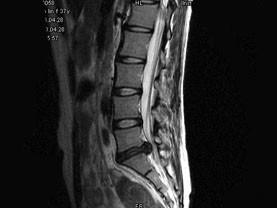

问题 女,37岁,腰腿痛半年,结合图像,选择最佳选项 ( )

选项 A、L~S椎间盘膨出 B、L椎间盘向后突出 C、L~S椎间盘向后突出 D、L~S椎间盘变性并向后突出 E、L~S椎间盘变性

答案 D